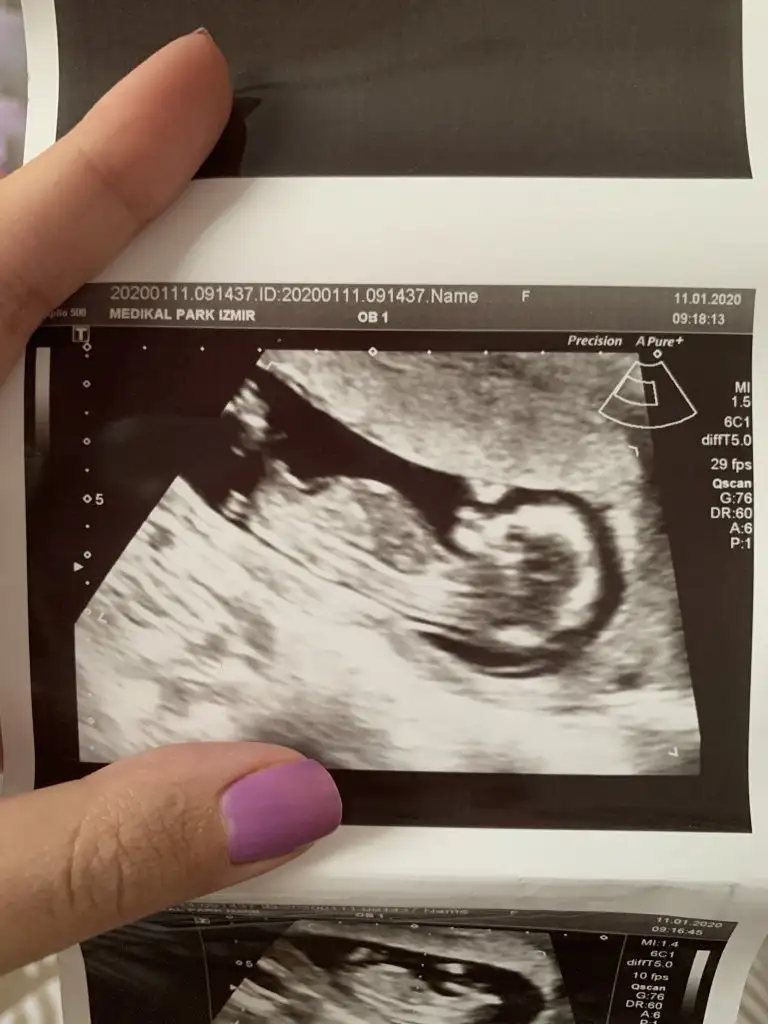

Net olmamakla birlikte kız siz yinede 12 haftayı paylaşın usg net degilTeyzeleri bize bakabilir misiniz acaba cinsiyet ne ola ki 11. Haftaya gireceğiz![]()

Kız gibi 12 haftayı paylaşın

Nubu biraz kapatmış bacagı ama sanki erkek gibi başka usg varmı 11 hafta yada 12+4 den başka usgMerhabalar ben de çok araştırdım bu teoriyi kız gibi geldi bana ama sizce nedir 12+4 ten ultraEki Görüntüle 2577076 Eki Görüntüle 2577077 son

Nubu kapalı görünmüyor başka usg varmı sanki eminde değilim kız gibi